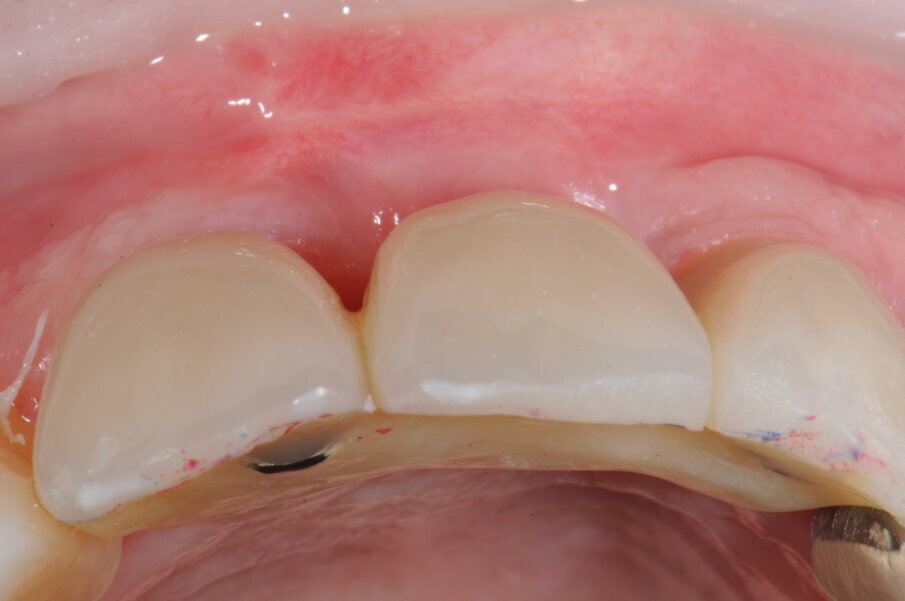

Trenta giorni dopo è stata rilevata l’impronta di precisione per la realizzazione di un provvisorio rinforzato in metallo che garantisse il ripristino della funzione masticatoria, estetica e fonetica (Figg. 20-25b).

Fig. 23 - Posizionamento della protesi provvisoria.

Figg. 24a, 24b - Protesi provvisoria in visione occlusale e frontale.

Figg. 25a, 25b - Valutazione dei tessuti molli in visione frontale e occlusale in assenza di protesi definitiva.